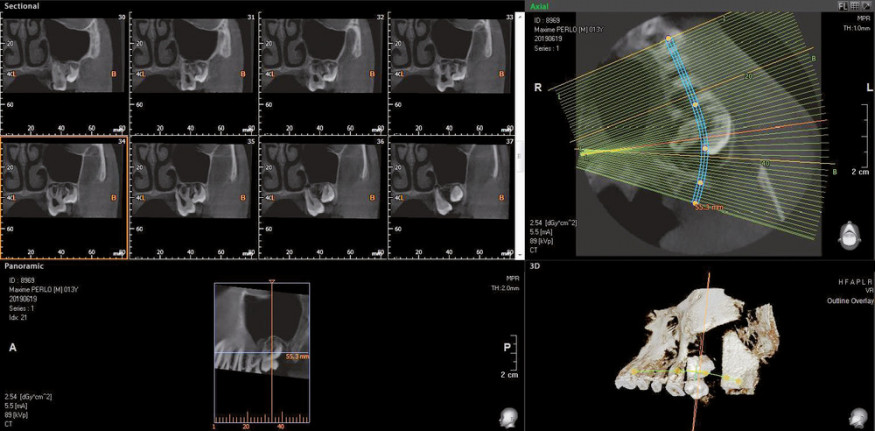

Sur le plan chirurgical, il est préférable d’extraire les dents de sagesse lorsque le tiers ou les deux tiers des racines sont édifiés. Il s’agit du stade où le geste est le moins compliqué et le moins risqué, donc où les suites chirurgicales sont les plus simples.

Cependant, il est parfois nécessaire d’intervenir plus tôt. C’est notamment le cas lorsque la dent de sagesse représente un obstacle à l’éruption de la deuxième molaire (fig. 1 et 2). Le cas échéant, un dégagement chirurgical avec collage d’une attache sur la deuxième molaire est souvent nécessaire, suivi d’une traction orthodontique.